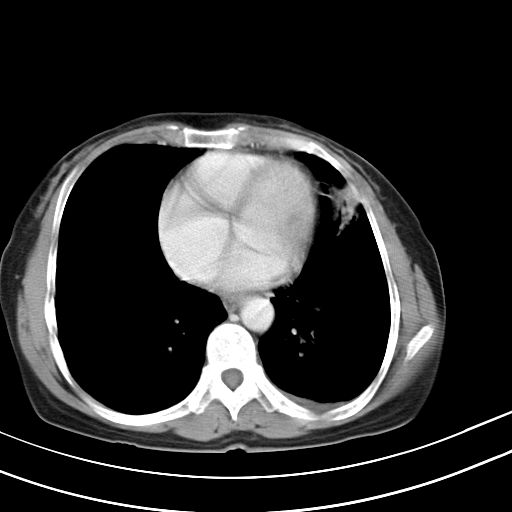

女,47岁,咳嗽胸痛一个星期,我们考虑肺结核,左下肺病灶肿瘤像不像,请高手指点。急。

右肺考虑炎症,建议抗炎后复查,左肺下叶考虑肺不张。

炎性灶;【1楔状实变影,有支气管气象,2近端纹理影增重】

右肺上叶前段积左肺舌叶炎症,建议严格抗炎后2周复查!

右肺上叶尖后段班片影不能出外肺结核。左肺舌叶三角形实变影,增强明显。考虑炎性病变

考虑两肺炎症,左胸腔积液,建议治疗后复查!

考虑炎性病变,左肺舌叶病灶需要与早期肺脓肿鉴别(结合实验室),左侧少量胸腔积液。

右肺为炎性改变,左肺病灶影像所见1、楔状实变影,边缘呈刀切样,见支气管气象,2、近端纹理影增重。

并从一元化来解释,还是符合炎性病灶。建议抗炎后复查。

两肺病变考虑炎症可能性大。(左肺病变呈楔状实变影,有支气管气象,近端纹理影增重)。

1)右肺上叶前段及左肺上叶舌段感染性病变;建议抗炎治疗后复查。2)左侧少量胸腔积液。

考虑右肺上叶前段及左肺舌叶炎症,建议抗炎治疗后复查除外结核。

左肺舌叶病灶呈扇形分布,其内可见支气管影,胸膜面光滑,不支持肿瘤病变。